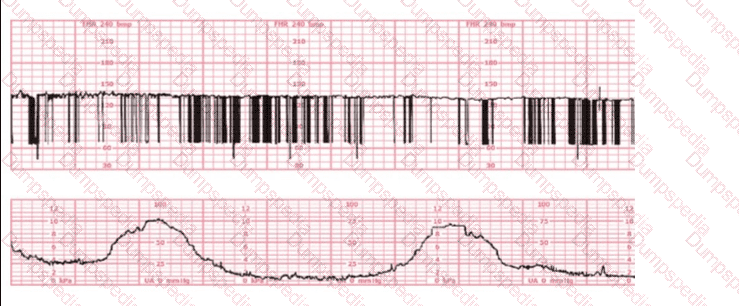

The decelerations seen in the fetal monitoring tracing shown are best described as:

The most probable underlying fetal physiologic cause for this tracing would be: